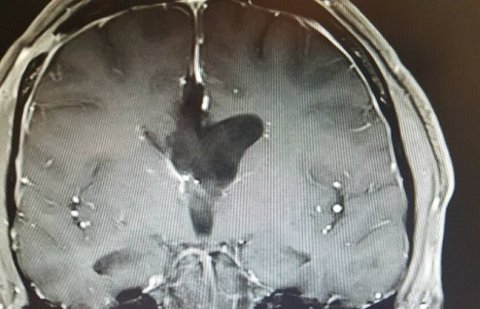

( 뇌종양 수술 전후 MRI 사진을 같이 올리겠습니다.  수술 전 사진 가운데 보이는 하얀색 덩어리가 뇌실에 있는 지름 6cm짜리 종양입니다. )